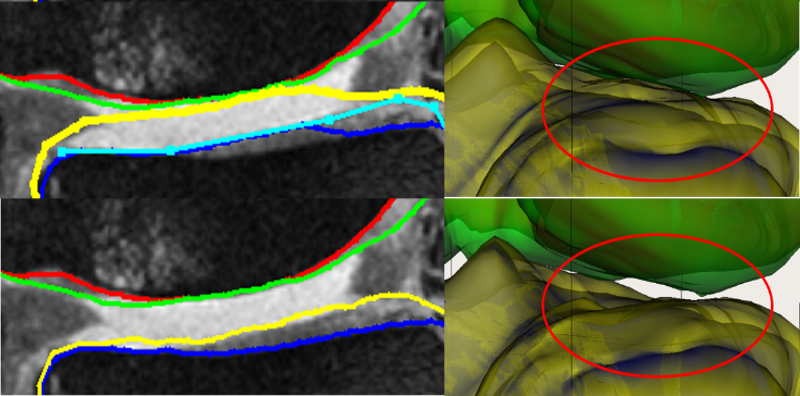

Fig. 8 qualitatively shows the improvement of 4D LOGISMOS over 3D. Note the lack of an obvious edge distinguishing the tibia and femur cartilage. Using the spatial and temporal contextual information from all the time-points, the 4D method is able to correctly position the cartilage for the tibia and femur despite the lack of image information locally.